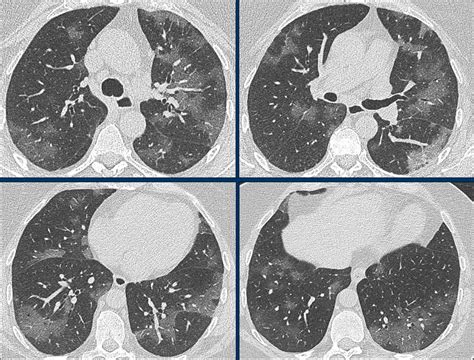

CT scans have become the "first line of defense" in diagnosing suspected infections, especially given the current shortage of testing.

How Does COVID-19 Appear in the Lungs? | Imaging ...